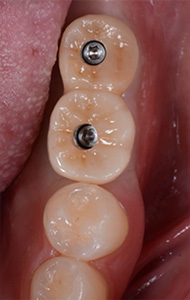

インプラントの被せ物はネジで装着、必要時は取り外し可能となります。

最終的にネジ穴は、白い樹脂で封鎖します。

上のネジ穴の写真やレントゲン画像から、インプラントが計画通りに埋入されて良好に終了していることが確認できます。